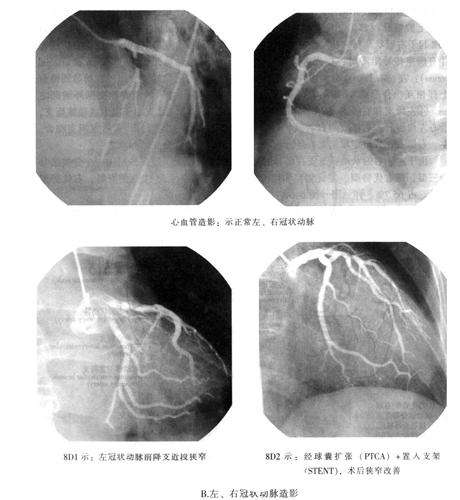

营养心壁的动脉有左、右冠状动脉,都是主动脉起始部的分支(图6-2A~D,图6-8A、B)。

图6-8 心脏的动脉(A、B)

图6-9 左、右冠状动脉(A)

图6-9 左、右冠状动脉(B)

据临床观察:心肌梗死左冠状动脉比右冠状动脉较为常见。故心肌梗死多发生于左心室的一定范围,其中左心室前壁、心尖部及室间前2/3,约占全部心肌梗死的50%,这些区域正是左冠状动脉前降支血供的解剖部位(图6-9A、B)。不难理解心肌梗死的解剖位置与闭塞的冠状动脉血供范围相一致。基于冠状动脉分布变异较大,故熟悉冠状动脉分布的相关变异,有临床参考意义。